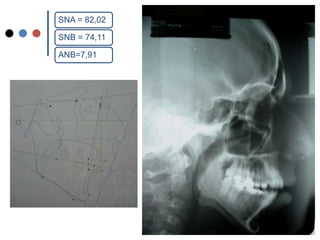

O documento apresenta registros odontológicos de um paciente ao longo de vários anos, incluindo panorâmicas iniciais e subsequentes, remodelações de arcadas dentárias superiores e inferiores ao longo de 7 meses, vedamentos labiais e registros de máxima intercuspidação e guias caninas nas datas listadas.